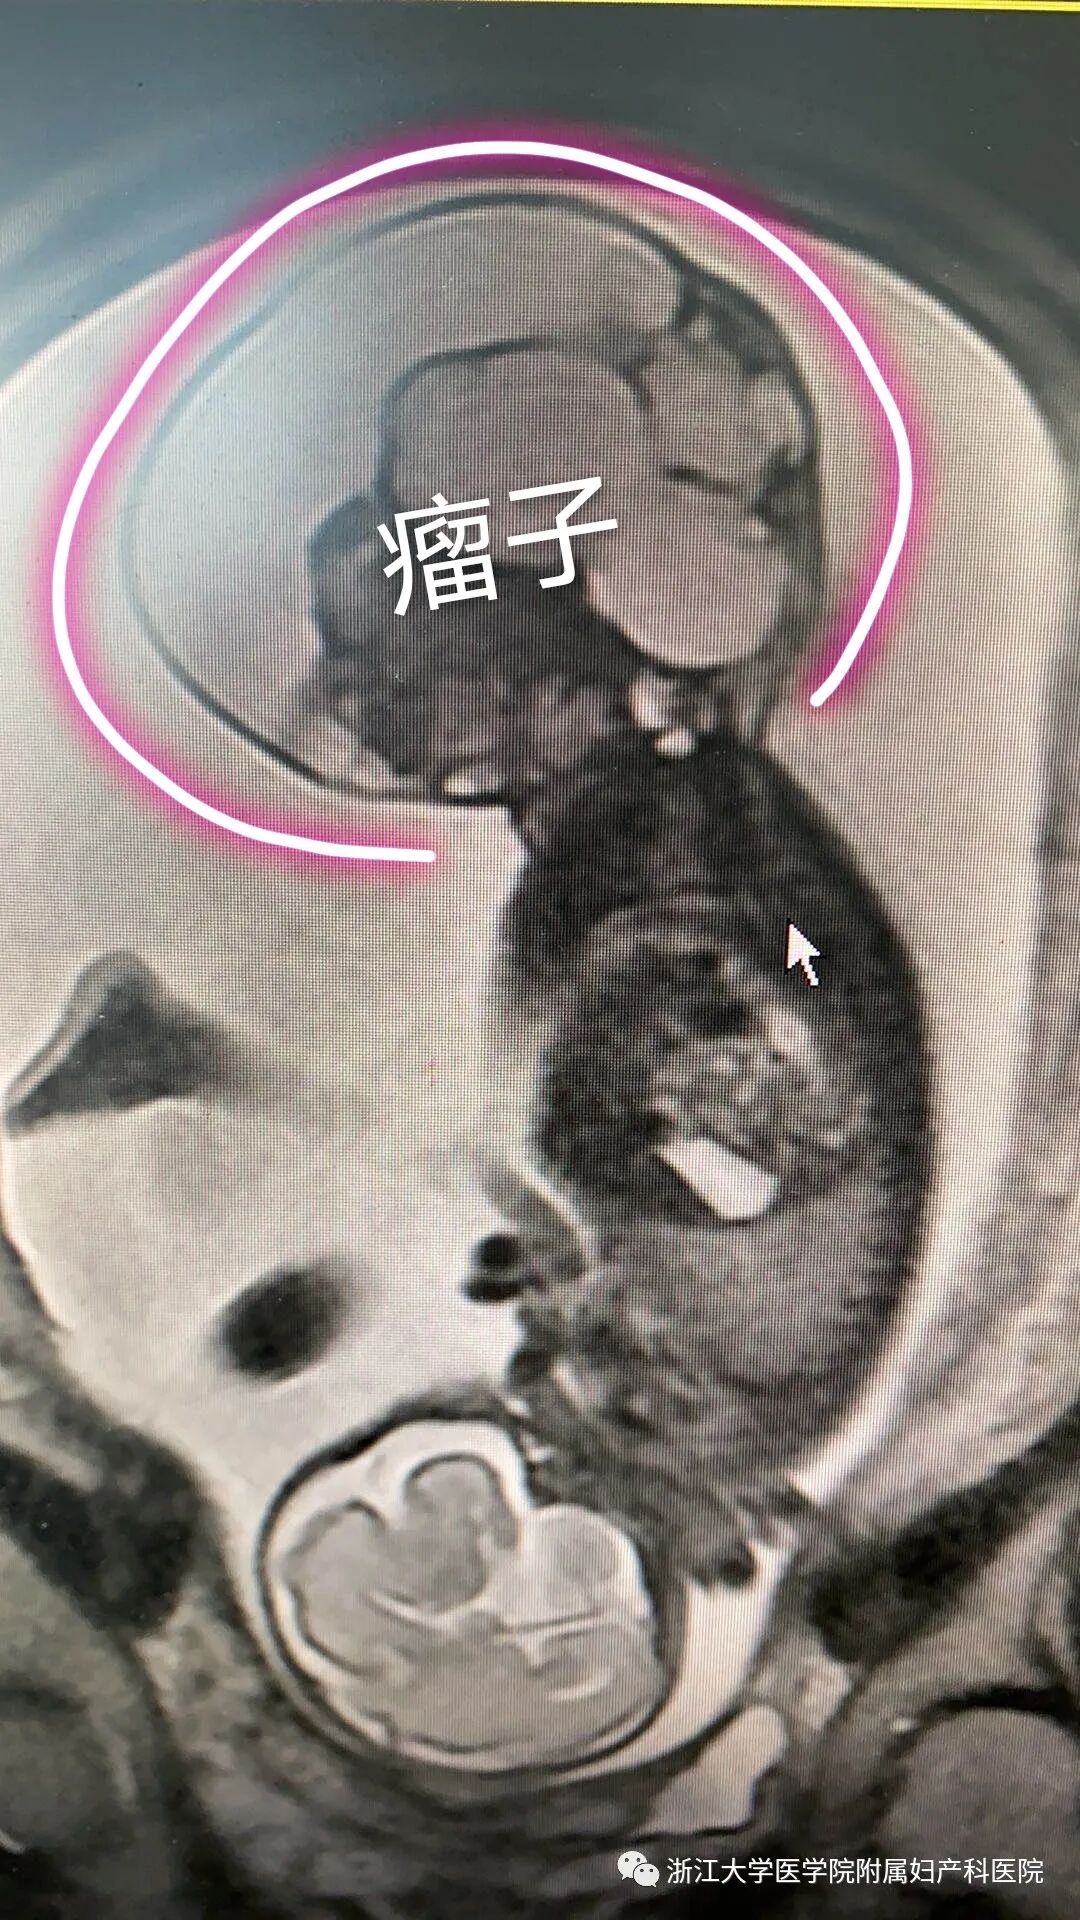

小美之前的产检都是很顺利的,就像其他一些到妊娠中期才发现宝宝异常的妈妈一样,20几周的三维检查显示,宝宝的骶尾部长了一个瘤子。

但是问题出在,这个畸胎瘤的生长速度太快了,30周左右的磁共振显示,因为畸胎瘤太大,它的发育也需要营养,所以就会跟宝宝“抢”。

畸胎瘤长在宝宝身上,血供来自胎儿,因此它是和宝宝共用一个支持系统的。瘤子太大,宝宝的心脏就要同时承担相当于“两个人”需要的功能,这对于心脏的压力就太大了。

小美宝宝的胎儿心超也证明了这一点——由于宝宝的心脏功能已经受损,瘤子的体积又太大,这样发展下去,宝宝很可能发生严重心衰。

最终,小美生下一个体重2200克的男婴,并切除一个体积14.2×16.5×11厘米,重达2065克,几乎跟宝宝一样大小的骶尾部畸胎瘤。